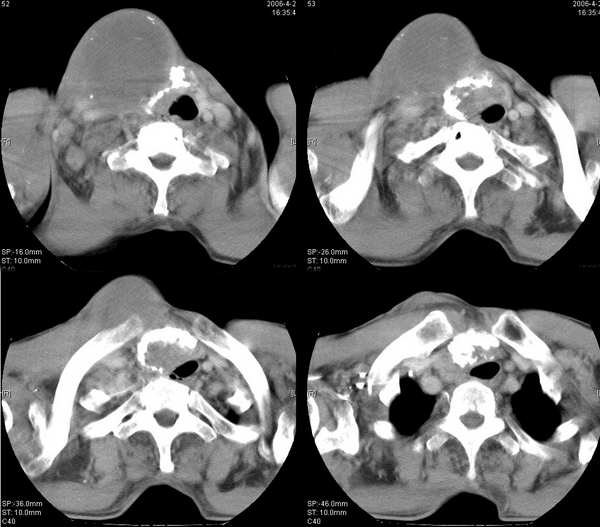

男,74岁,甲状腺肿30余年。现右颈部出现新肿块,疼痛,感乏力。

右颈部巨大软组织肿块影,范围较广,上至下颌角,下至颈静脉切迹。其最大层面位于右侧甲状腺区。肿块密度不均,其中有坏死液化区和班片状钙影,增强扫描见肿块实质区有强化。邻近结构挤压移位,部分结构侵蚀破坏,右侧多个颈深淋巴结肿大。两肺弥漫分布小结节影,以胸膜下为主,其大小不等,边缘光整。右侧胸壁亦见软组织结节影,纵隔多个淋巴结肿大及两侧锁骨上淋巴结肿大。

意见:右侧甲状腺癌并两肺、胸壁、纵隔淋巴结、颈深淋巴结、锁骨上淋巴结等广泛转移。